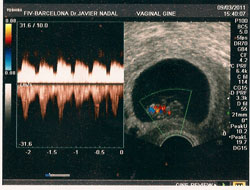

En un proceso de FIV, la mujer debe realizar un tratamiento de estimulación ovárica con medicamentos inductores de la ovulación, cada día más puros y eficaces, para intentar conseguir el máximo número de folículos. Estos tratamientos son siempre personalizados para cada paciente y dependerán de factores como la edad y de los resultados de las analíticas hormonales previas, y supervisados siempre con controles ecográficos y analíticos.

Una vez los folículos alcancen el número y el tamaño idóneo, se administra una nueva medicación para provocar la maduración ovocitaria.

A las 35-36 horas se realiza bajo sedación y por vía ecográfica, la extracción de los óvulos. En el laboratorio de FIV, se inseminan estos óvulos con los espermatozoides de la pareja, o si fuera necesario con banco de semen, para intentar conseguir el máximo de embriones.